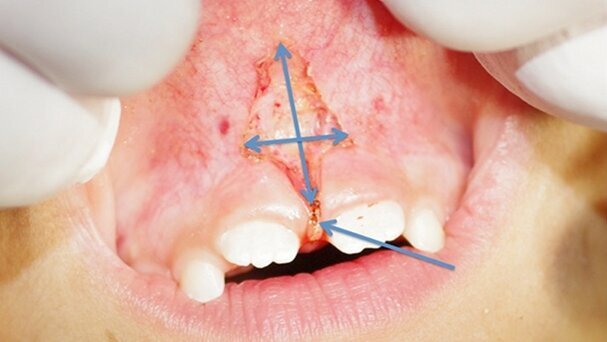

Une enfant de 7 ans adressée par l’orthodontiste. L’examen clinique montre un frein de Type 4, le test de traction induit une mobilité de la papille incisive. Les fibres du frein passent entre les incisives et viennent s’insérer en palatin sur la papille bunoïde.

La lèvre est maintenue sous tension et le premier trait d’incision est pratiqué dans l’axe du frein, tout en maintenant une légère traction de la lèvre supérieure. La seconde incision est pratiquée perpendiculairement à la première et vise à sectionner les fibres horizontales du frein labial.

La dernière intervention consistera à « effacer » l’insertion papillaire du frein par gommage. L’absence de saignement permet un contrôle visuel total durant toute l’intervention qui s’est déroulée en moins de 3 minutes, avec une coopération totale de la patiente.

Après avoir pratiqué la double incision en croix, il est réalisé un gommage de l’insertion médiane du frein quasiment jusqu’au contact osseux sur la face vestibulaire du processus alvéolaire, et au niveau du sommet de la crête osseuse avec retour en palatin.